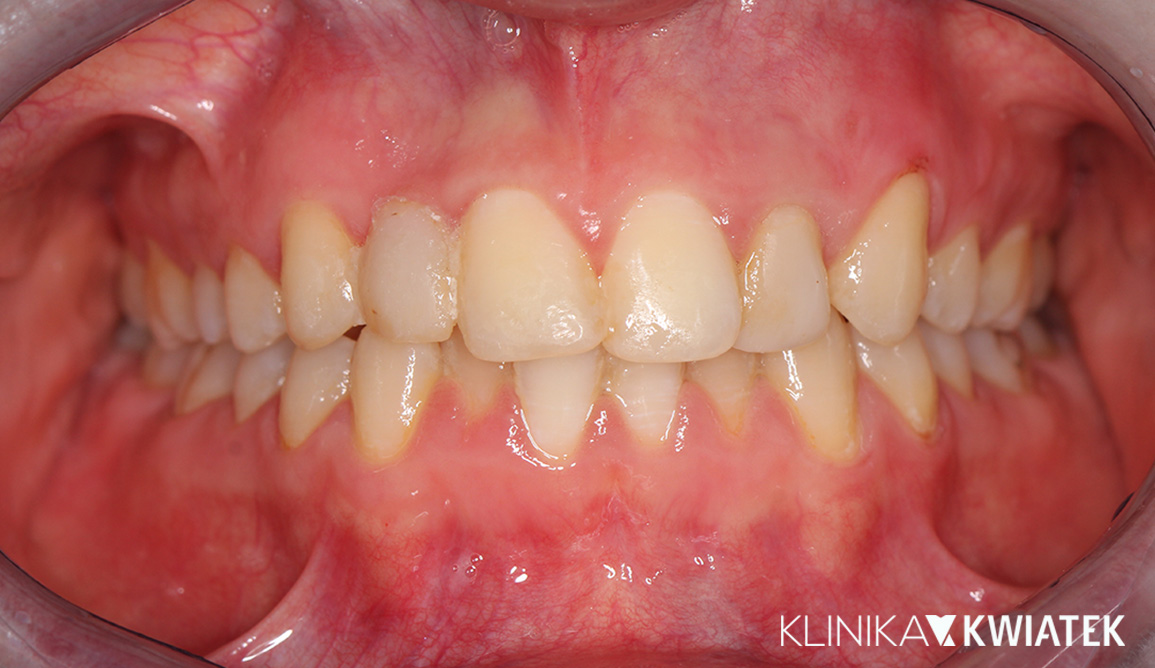

Kliniczna precyzja i estetyka – jak przywróciliśmy funkcję i piękno uśmiechu

Pacjentka zgłosiła się z wadą zgryzu, licznymi ubytkami i utraconymi zębami trzonowymi, co powodowało trudności w żuciu i estetyczne niezadowolenie. Leczenie obejmowało ekstrakcje, ortodoncję, implantację oraz kompleksową rekonstrukcję protetyczną. Po kilkunastu miesiącach terapii Pacjentka odzyskała pełną funkcję zgryzu i piękny, harmonijny uśmiech.